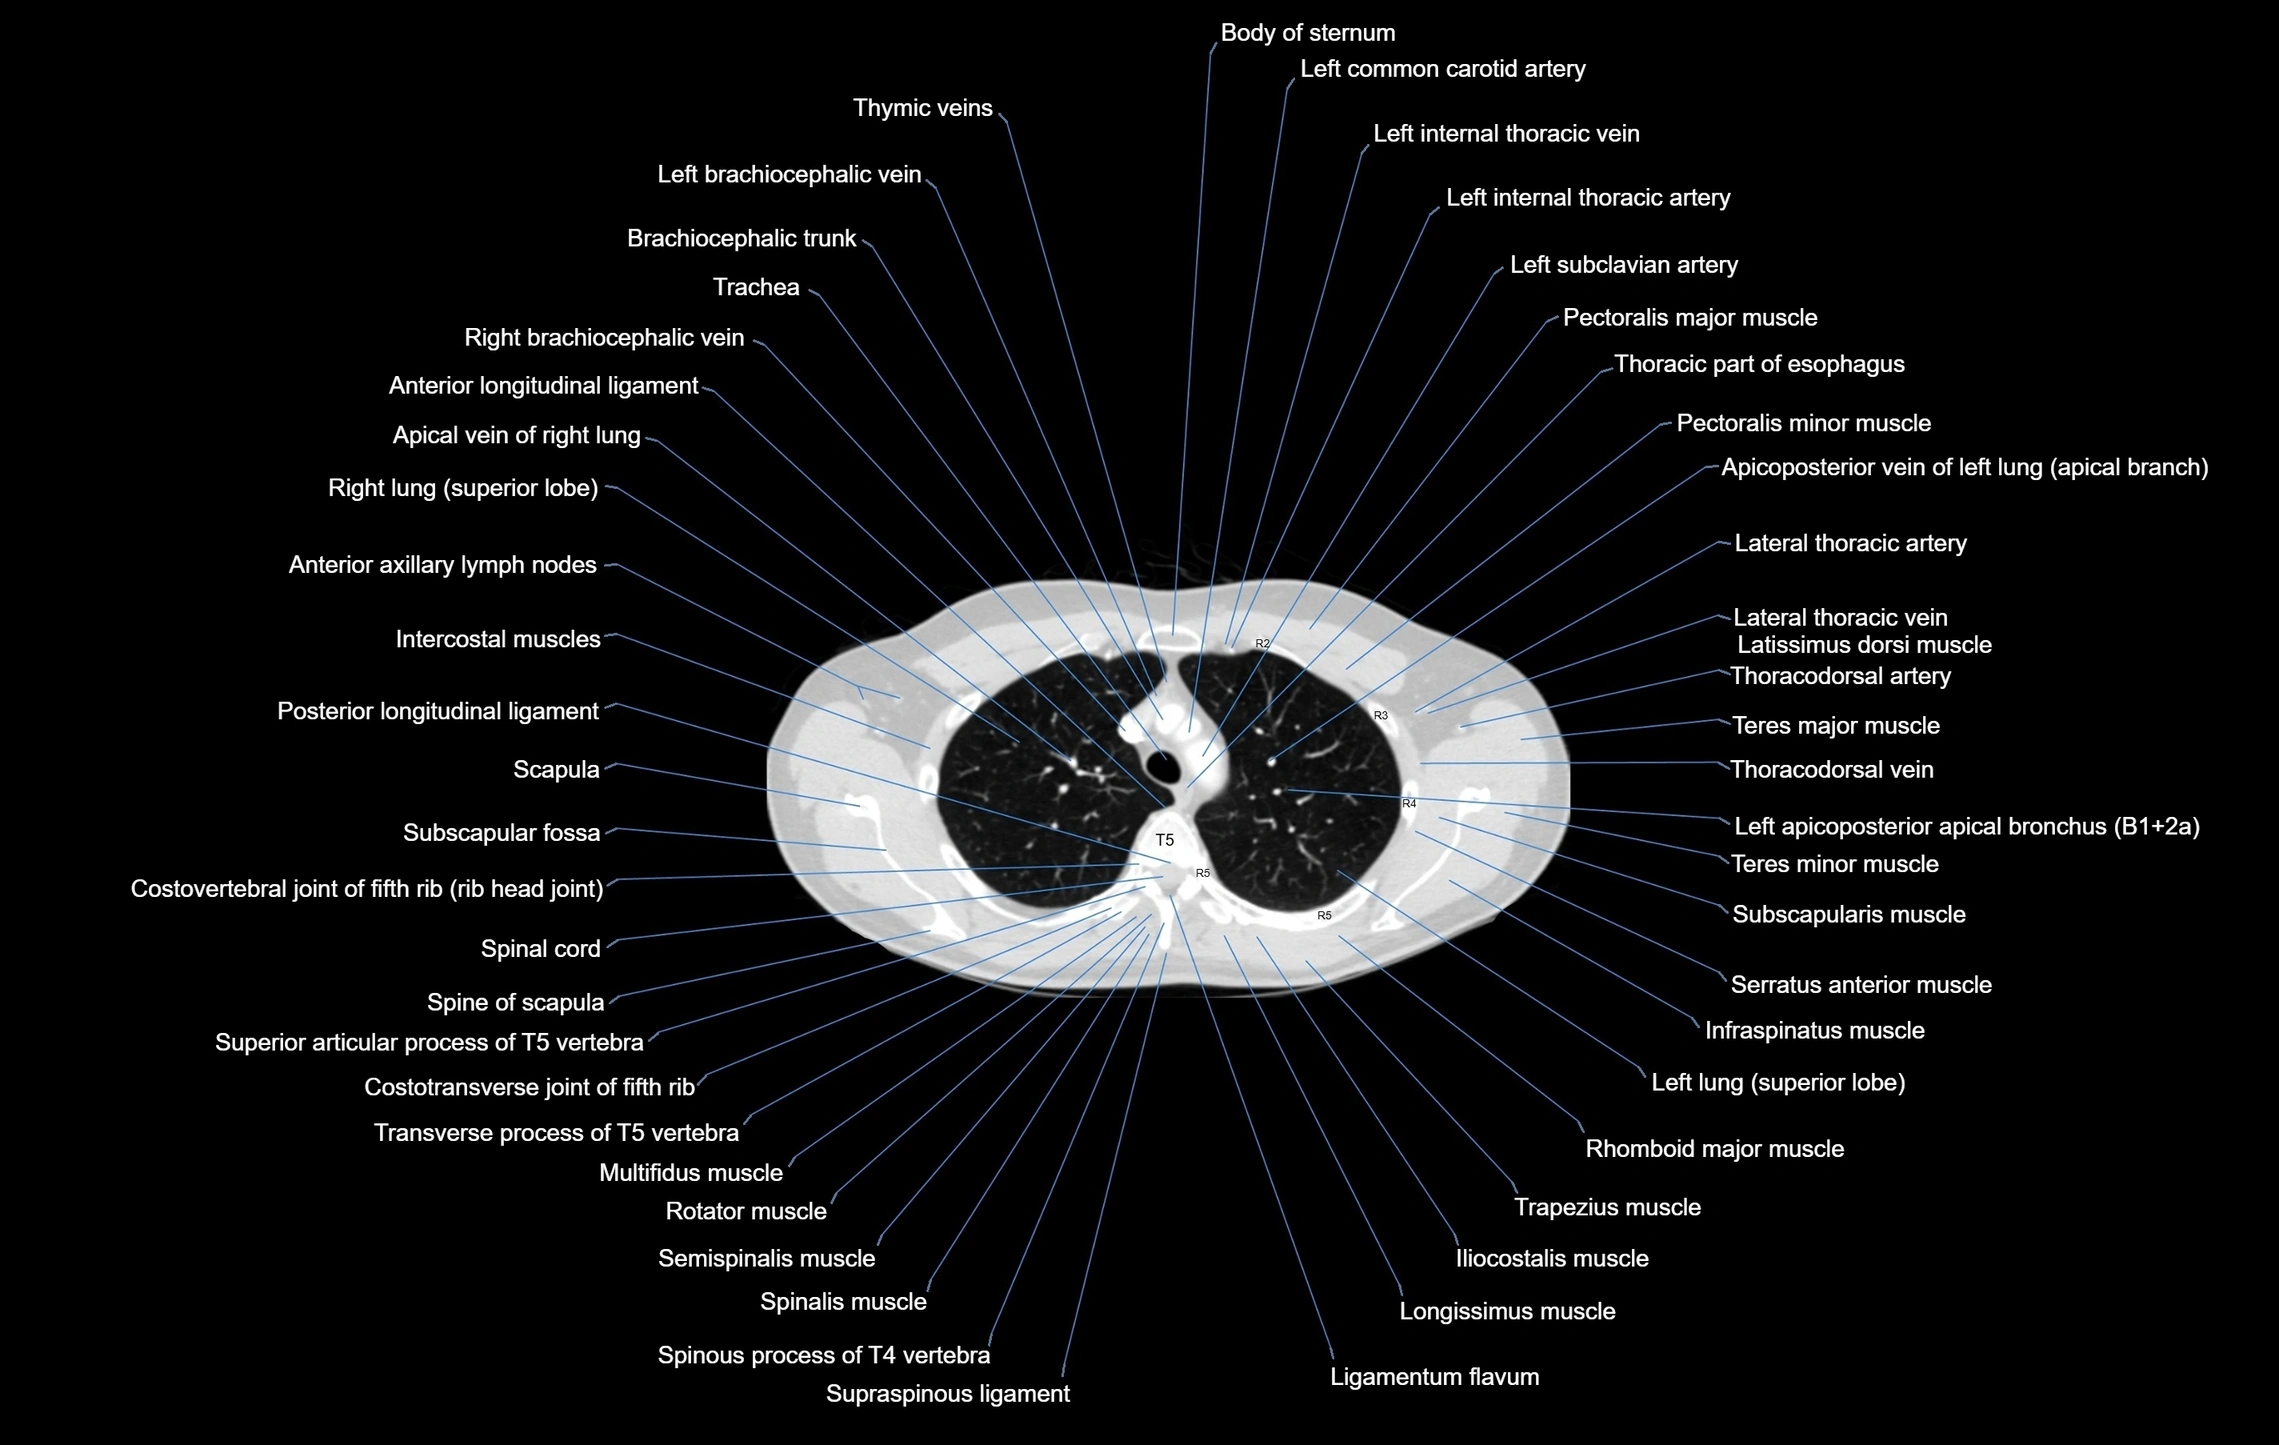

- Body of sternum

- Brachiocephalic trunk

- Left common carotid artery

- Left internal thoracic artery

- Left brachiocephalic vein

- Right brachiocephalic vein

- Trachea

- Pectoralis minor muscle

- Pectoralis major muscle

- Serratus anterior muscle

- Infraspinatus muscle

- Rhomboid major muscle

- Subscapularis muscle

- Teres major muscle

- Teres minor muscle

- Spine of scapula

- Scapula